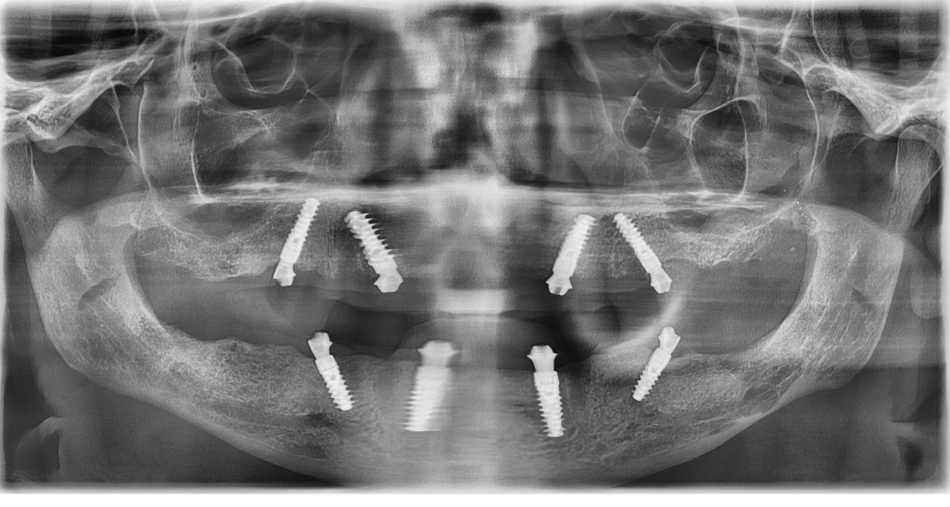

Es erfolgen umfangreiche Aufklärungsgespräche mit dem Patienten bezüglich der möglichen Behandlungsalternativen unter fortwährender Einbeziehung des familiären Umfelds. Spezielles Augenmerk wird auf die Aufklärung über parodontalpathogene Mechanismen gelegt, die Einordnung seines Verhaltens gegenüber zahnärztlicher Therapie in der Vergangenheit und die daraus für ihn zu ziehenden Schlüssen für die Zukunft nach Abschluss einer implantatprothetischen Rehabilitation. Unter Abwägung aller Chancen und Risiken entscheiden sich Patient und Behandler gemeinsam für eine Pro-Arch-Versorgung in beiden Kiefern. Auf Wunsch des Patienten geschieht dies nicht in Intubationsnarkose, sondern in i.v.-Sedierung (Midazolam®) in zwei getrennten Sitzungen zur Vermeidung einer Überschreitung der Grenzdosis des Lokalanästhetikums. Nach einer klinischen und röntgenologischen Untersuchung (PSA) zeigte sich ein final parodontal destruierter Restzahnbestand (Abb. 5) sowie ein retinierter und verlagerter Zahn 28. Im angefertigten DVT weisen die unbezahnten Kieferabschnitte eine horizontale und vertikale Atrophie auf. Der anteriore Bereich der Maxilla als auch der Mandibula waren ausreichend dimensioniert für die Aufnahme von jeweils vier Straumann BLX®-Implantaten in ausreichenden Längen und Durchmessern. Die prothetische Vorplanung (Wax-up) erfolgte nach Abdruck und Modellherstellung und orientierte sich an älteren Fotos.

Das Eindrehmoment lag zwischen 40 und 60Ncm. Die Implantate wurden mit Screw-retained-Abutments (SRA`s) versorgt (O°, 30°) (Abb. 10). Im Anschluss an den Wundverschluss erfolgten Abdrucknahme (Impregum® 3M Espe, Löffel: Miratray®) (Abb. 11) und Bissregistrierung (individuelle Bisschablone, Occufast®, Zhermak). Zuletzt wurden die Zähne 33 und 43 entfernt. Das aus Kaltpolimerisat hergestellte mit Glasfaser verstärkte Langzeitprovisorium (Abb. 12) wurde nach ca. 3 Stunden eingegliedert (Abb. 13 OPG Post OP UK). Zum Zeitpunkt der Nahtentfernung nach einer Woche zeigte sich eine weit fortgeschrittene Heilung.

Nach ca. 5 Monaten erfolgte eine röntgenologische Kontrolle der Osseointegration (Abb. 20, 21).